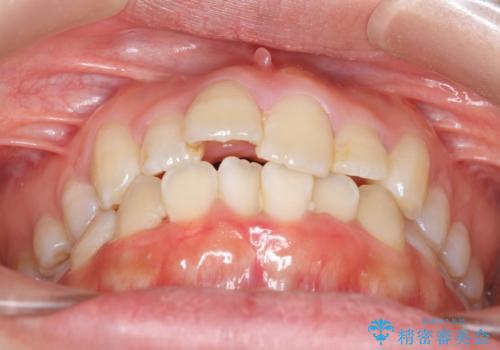

でこぼこ 八重歯をきれいに

- 八重歯を気にして来院されました。

歯のがたがたがあったため、上下の小臼歯を抜いて治療しました。

犬歯(糸切り歯)はすべての歯の中で歯根が一番長く、安易に抜かずに並べていくことは大変重要なことです。

八重歯は最初の半年くらいで改善し、見た目はだいぶ良くなりました。